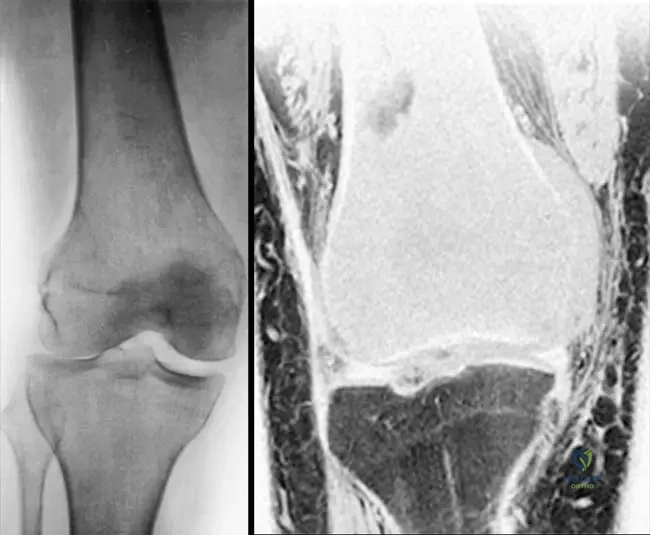

Rationale: The clinical context for Fig. 8.22 a, b explicitly links "Short stature and osseous deformity secondary to Ollier’s disease" with multiple enchondromas. Ollier's disease is characterized by multiple enchondromas, often unilateral, leading to significant skeletal deformities and growth disturbances. The other conditions are distinct skeletal dysplasias or disorders not primarily characterized by multiple enchondromas.

Rationale: The clinical context for Fig. 8.22 a, b explicitly states "Short stature and osseous deformity secondary to Ollier’s disease." Ollier's disease is characterized by multiple enchondromas, often unilateral, leading to significant skeletal deformities and growth disturbances. Solitary enchondroma does not involve multiple lesions. Maffucci syndrome includes hemangiomas, not mentioned. Chondrosarcoma is malignant. Fibrous dysplasia is a different bone disorder.

Rationale: The presence of multiple enchondromas, often unilateral or asymmetric, leading to skeletal deformities and limb length discrepancies, without associated soft tissue hemangiomas, is characteristic of Ollier's Disease (enchondromatosis). Maffucci Syndrome is similar but includes soft tissue hemangiomas. Multiple Hereditary Exostoses involves osteochondromas (exostoses), not enchondromas. Fibrous dysplasia has a "ground-glass" appearance. Chondrosarcoma is a malignant tumor, though it can arise from enchondromas, the primary diagnosis here is the underlying syndrome.